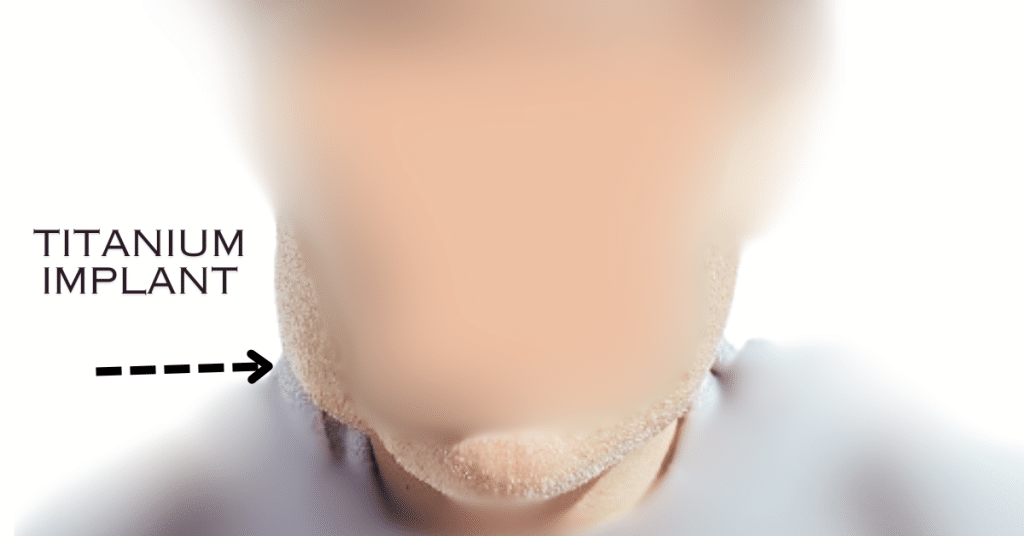

Fig. 1

Unedited image illustrating the effects of Capsular Contracture observed “pockets” 6-7 months post-surgery. A hematoma was detected the day after implantation, contributing to the complication.

Facial implants have the potential to significantly enhance appearance; however, a critical and under-discussed complication is Capsular Contracture, and “pockets.” Unlike the more widely recognized Capsular Contracture associated with breast implants, this issue in facial implants has remained obscure and largely unacknowledged—until now.

Capsular Contracture occurs when the body forms a dense, fibrous capsule around an implant, resulting in rigidity and discomfort. This condition can lead to significant pain and aesthetic complications, with the added risk of infection emerging months after implantation and recurrent swelling that may persist for years.

“Pockets” refer to the spaces formed around the implant during surgery, often presenting as a hematoma surrounding the implant. These pockets are the precursors to Capsular Contracture. The inability of the tissue to heal normally exacerbates this issue, leading to persistent swelling and the subsequent hardening process that characterizes Capsular Contracture. This condition often results in recurring infections, further complicating the healing process.